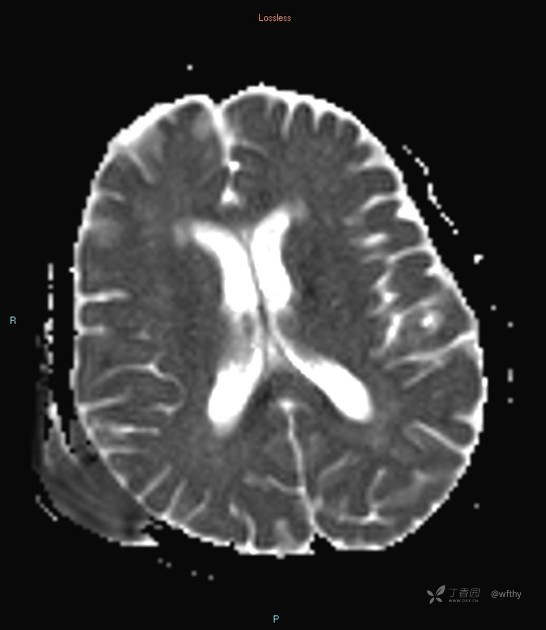

病例女65,头部肿块